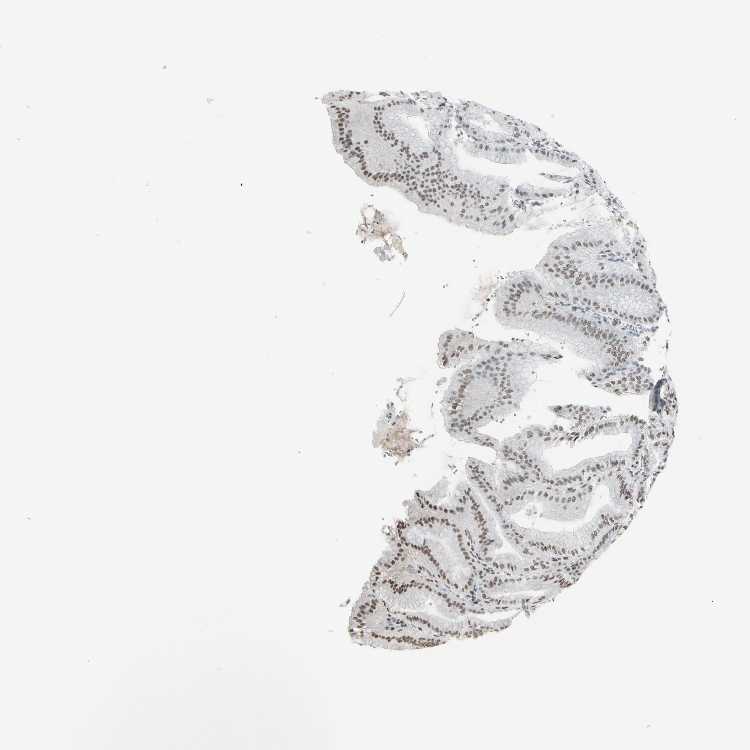

STOMACH 1 - Antibody stainingi

Antibody staining in the annotated cell types in the current human tissue is reported as not detected, low, medium, or high, based on conventional immunohistochemistry profiling in selected tissues. This score is based on the combination of the staining intensity and fraction of stained cells.

Each image is clickable and will lead to virtual microscopy that enables deeper exploration of all samples and also displays staining intensity scores, fraction scores and subcellular localization as well as patient and tissue information for each sample.

Antibody HPA064033Antibody CAB010066

Glandular cells HighHigh